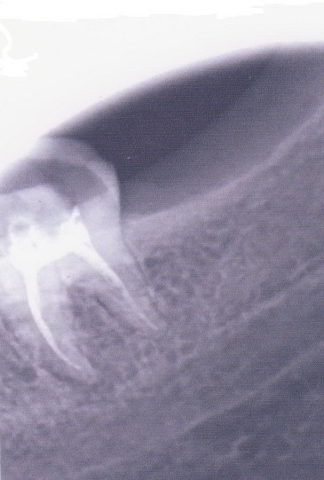

Примеры лечения радикулярных кист челюстей без скальпеля:

Фото: до лечения депофорезом

Фото: после лечения депофорезом